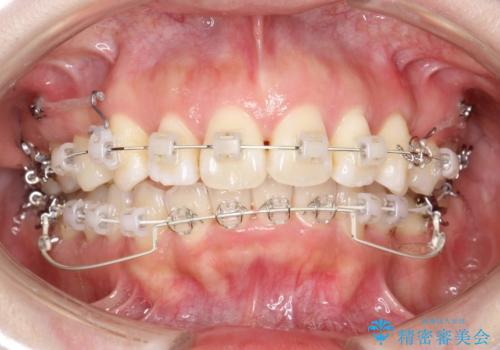

- 矯正装置

- 審美装置

抜歯矯正は抜歯にできたスペースをつかい、前歯を積極的に下げたり、大きなガタつきを取り除くことができますが、その分時間がかかります。

ワイヤーを用いることで、矯正中に生じる様々な問題にその場で対処することができます。